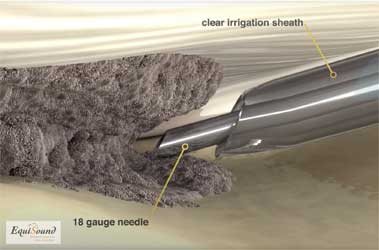

Tenex est une technique de traitement développée il y a 5 ans aux États-Unis pour traiter des pathologies tendineuses chroniques chez l’être humain (atteinte chronique des tendons d’Achille, épine calcanéenne, dégénérescence du tendon rotulien, etc.). Cette technique utilise des ultrasons (comme pour un détartrage) afin de détruire le tissu endommagé et de stimuler ainsi le processus de cicatrisation pour offrir une nouvelle chance de guérison. La fréquence ultrasonore est spécifiquement choisie pour ne détruire que les tissus durs (fibrose et minéralisations) et ne pas causer de dommages au tissu tendineux sain. Le traitement par ultrasons est appliqué à l’aide d’une aiguille creuse dans un tube creux (cf. photo 8a). Durant le traitement, un flux de NaCl sort de l’aiguille creuse et est simultanément aspiré via le tube creux (cf. photos 8b et 8c). Cette solution aqueuse permet avant tout l’évacuation du tissu débridé mais aussi le refroidissement de l’aiguille qui chauffe fortement en raison des ultrasons.

L’aiguille étant introduite de manière échoguidée via des incisions de ponction dans la peau, ce traitement est mini-invasif. De ce fait, le patient récupère plus rapidement et nécessite peu de soins de plaie. Ceci permet aussi le positionnement exact de l’aiguille dans la zone dégénérative de la structure pathologique.

Chez le cheval, la technique peut être réalisée aussi bien sur patient debout (photos 7a, 7b et 2b) que sous anesthésie générale (photo 6). Chez le patient debout, il faut une asepsie stricte, une sédation adéquate par perfusion continue (CRI) et une anesthésie de la jambe afin de pouvoir travailler en toute sécurité. Lors d’interventions étendues, lors du traitement d’un membre postérieur ou en présence de patients dangereux par exemple, on optera dans certains cas pour un traitement sous anesthésie générale. Chez le chien, nous réalisons cette procédure sous forte sédation et avec une anesthésie locale adéquate de la peau, ou sous anesthésie générale. Après l’intervention, les ports d’accès sont refermés à l’aide d’un point simple ou d’une agrafe. Ces ports sont parfois tellement petits qu’il n’est pas nécessaire de les suturer.